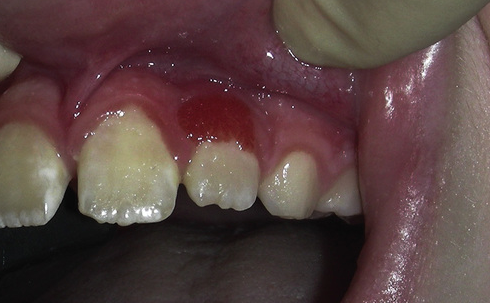

What is the likely diagnosis?

Localized spongiotic gingival hyperplasia.